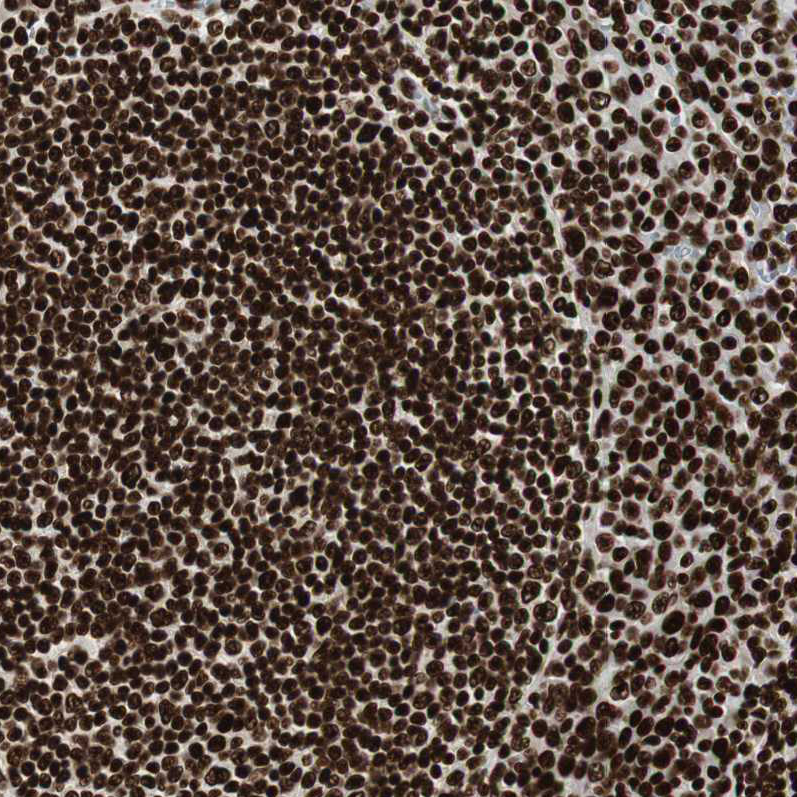

Immunohistochemical staining of human placenta shows strong nuclear positivity in trophoblastic cells.